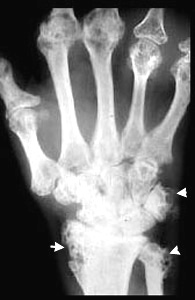

Sarcoidosis

Punched out lesions in bone